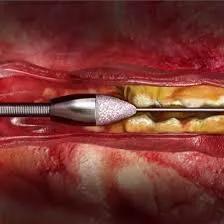

- IVL ( لیتوتریپسی داخل عروقی)

- ادونس اینترونشن